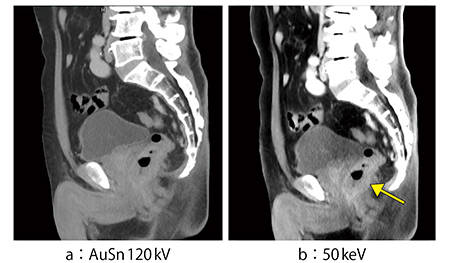

症例4は,直腸がん症例である。AuSn120kVの平衡相(図6 a)では,わずかに直腸の壁が濃染しているのが認められるが,50keV画像(図6 b)では濃染が明らかである。サジタル画像(図7)では前立腺との境界もはるかに観察しやすく,腫瘍の浸潤度判定にきわめて有用である。

図7 症例4のサジタル画像